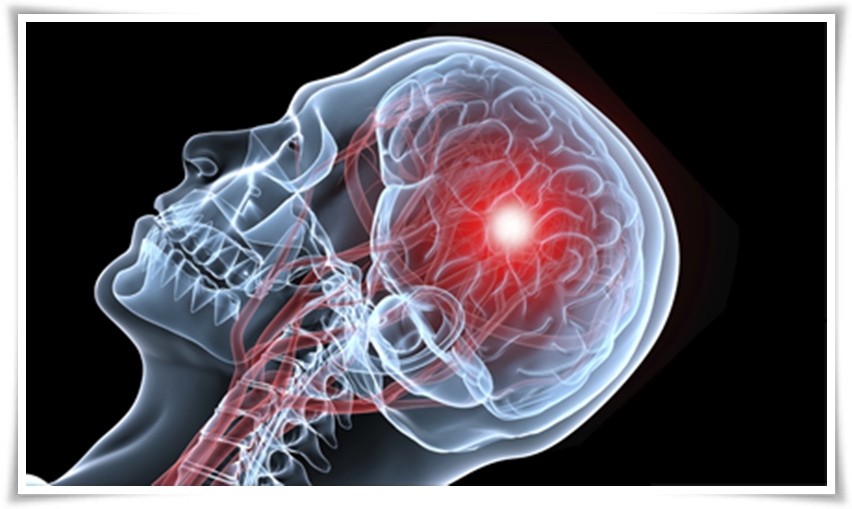

뇌졸중은 뇌경색인지 뇌출혈인지에 따라 판단 역시 다르게 나타납니다. 뇌줄중 환자의 열 명 중 여덟 명은 뇌경색을 가지고 있으며 심장에서 혈액 이동을 막는 혈전이 생기기 때문에 뇌에도 원활한 혈액 공급이 되지 않아 뇌혈관이 막히며 문제가 발생하며 뇌출혈은 열 명 중 두 명꼴로 나타나는데 뇌 신경 손상만 있는 것이 아니라 혈액이 뇌 속에 고여 조직을 압박하거나 충격을 주기도 하는데 결국 혈액을 운반하는 혈관 건강이 좋지 않아지면서 나타나는 뇌졸중 역시 서구화된 식습관과 생활습관으로 고지혈증과 같은 심혈관계 질환으로 동맥경화가 유발되며 나타나고 있어 주의가 요구됩니다.